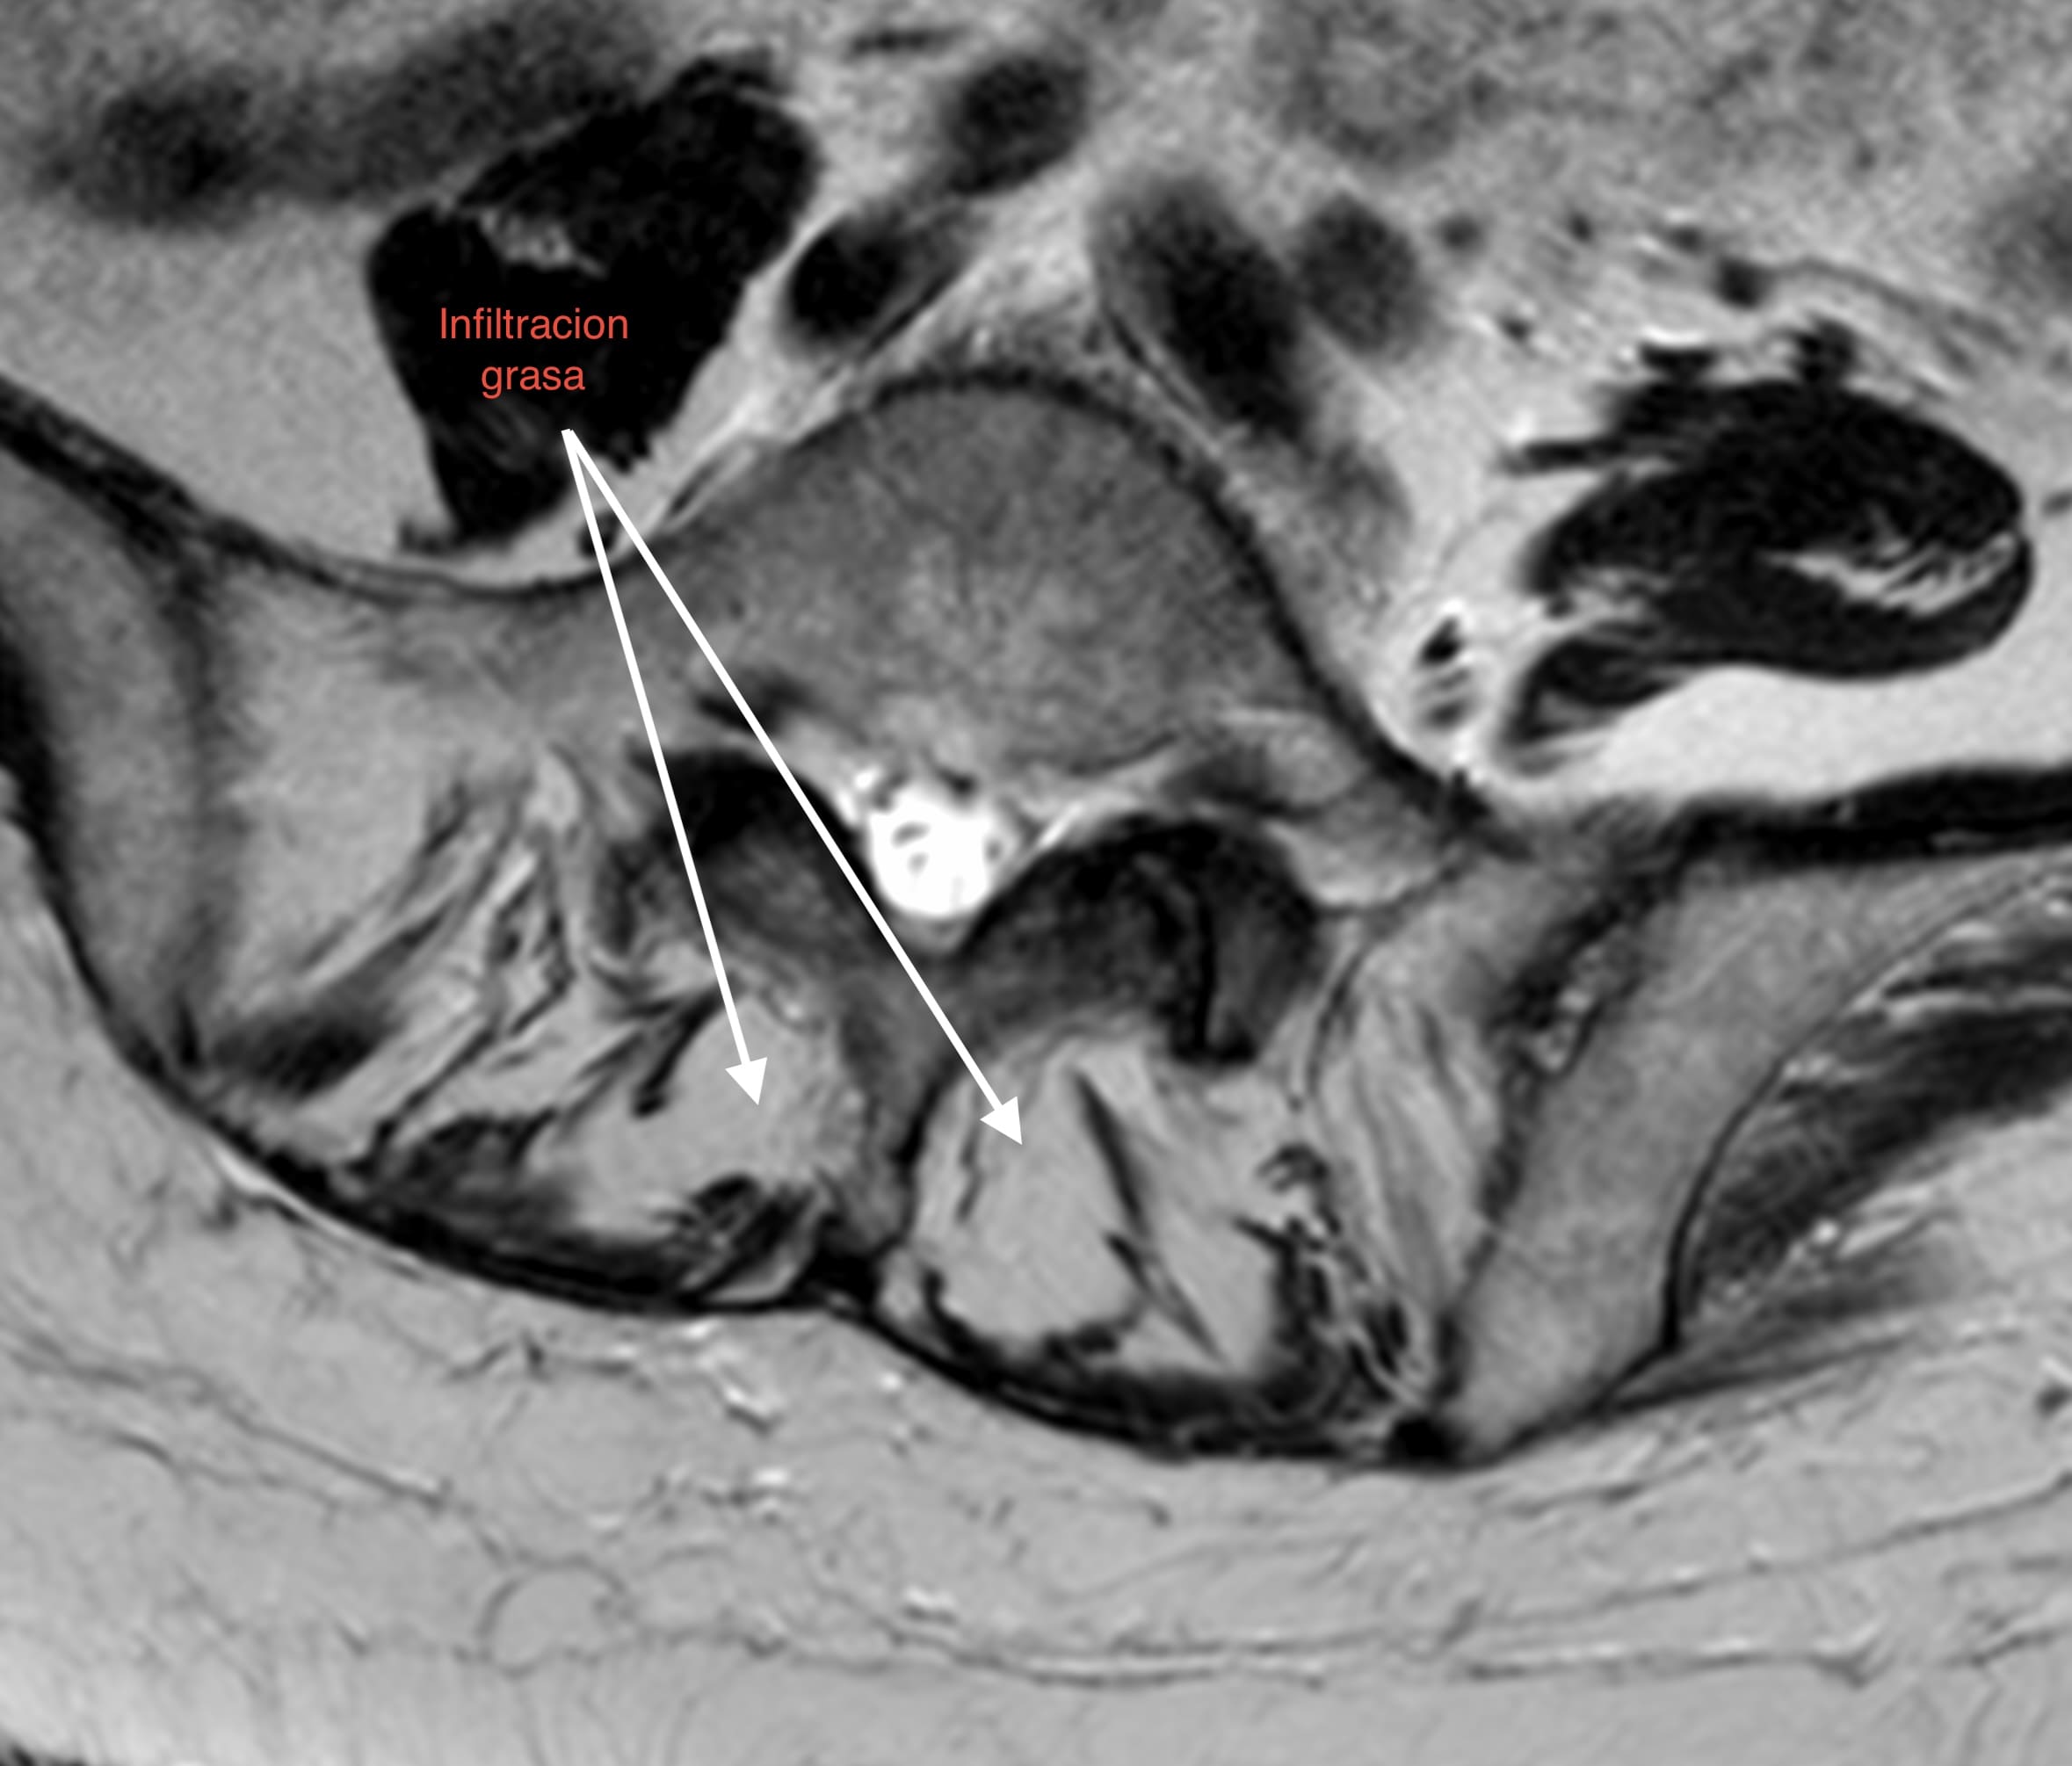

1. Pérdida del «Tirante» Dinámico: Los músculos multífidos actúan como estabilizadores segmentarios finos. En pacientes sarcopénicos, estos músculos son reemplazados por tejido adiposo no contráctil, perdiendo su capacidad de tensión.

• Calidad vs. Cantidad: La infiltración grasa (clasificación de Goutallier o medición de unidades Hounsfield en TAC) en el multífido es un factor de riesgo independiente para la reintervención. Músculos con alta infiltración grasa se correlacionan con peores resultados funcionales (ODI) y mayor tasa de complicaciones mecánicas como la cifosis de la unión proximal (PJK).

1. Screening Preoperatorio Rutinario: La RM lumbar debe utilizarse para evaluar la calidad muscular (corte axial en L3/L4), no solo la patología neural.